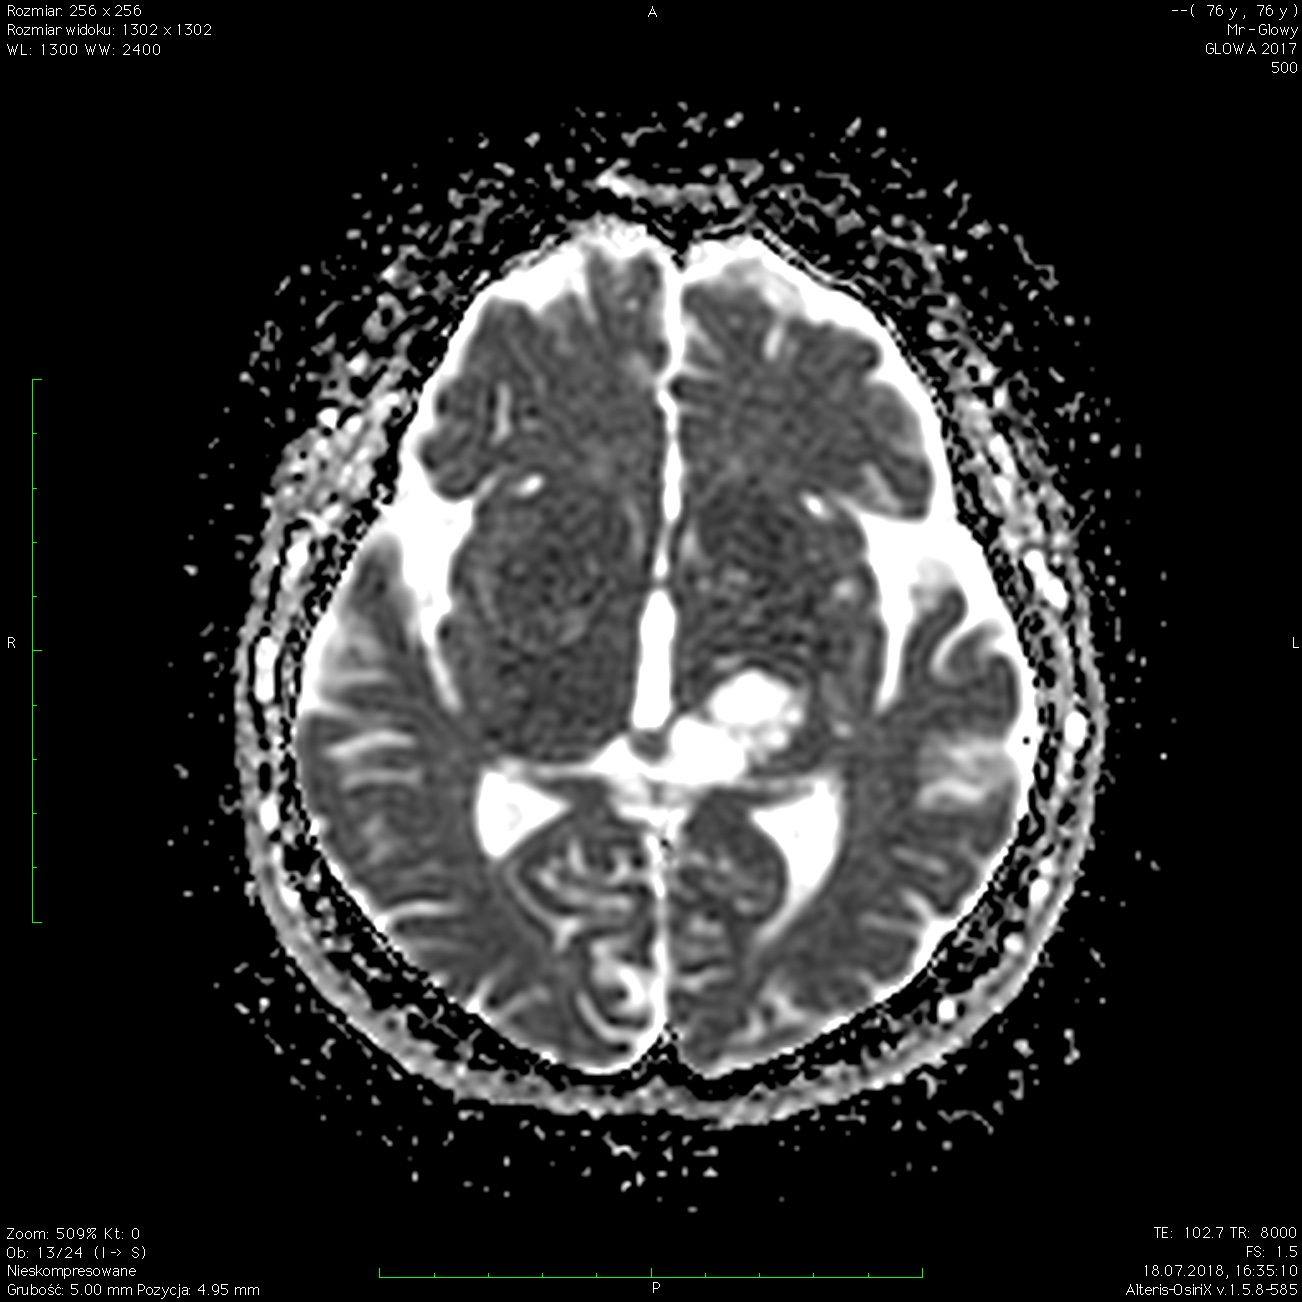

W przyśrodkowej części lewej półkuli mózgu, w okolicy lewego wzgórza, lewej torebki wewnętrznej i lewego konara mózgu, widoczna jest nieregularna policykliczna zmiana o płynowych wartościach sygnału z licznymi przegrodami, o wymiarach ok. 27x15x32 mm, nieulegająca wzmocnieniu kontrastowemu. Zmiana wydaje się łączyć z okolicą zbiornika blaszki czworaczej po stronie lewej.

Obraz może odpowiadać torbielom wzgórza.